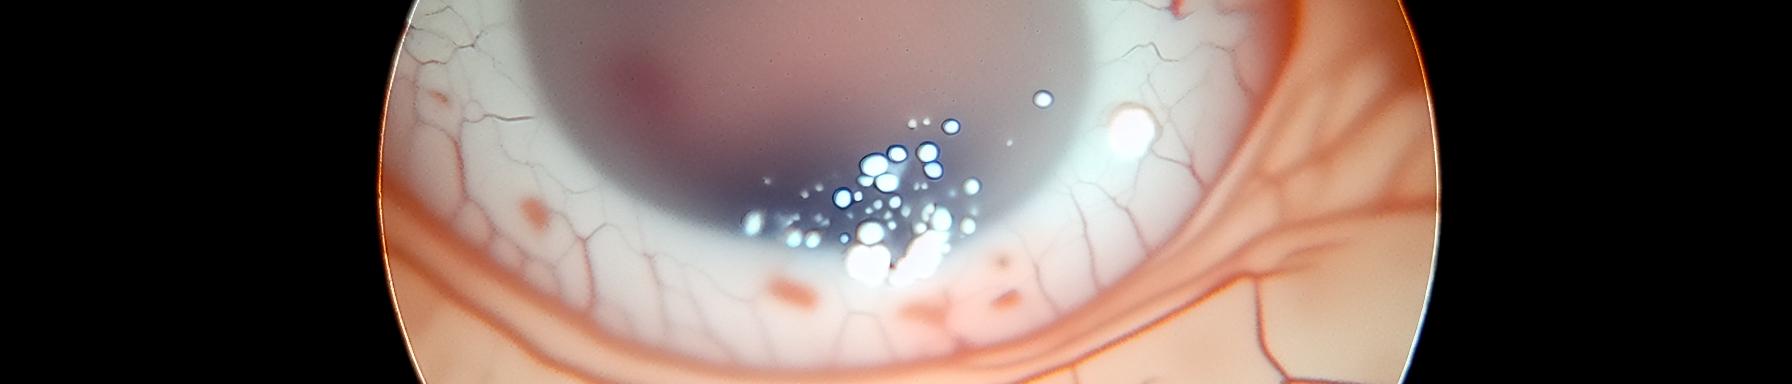

Keratoconjunctivitis is a combination of conjunctivitis and keratitis that results in simultaneous inflammation of the conjunctivitis and cornea of the eye. It results from bacterial and viral factors, however, keratoconjunctivitis can also be the consequence of the complication of conjunctivitis. Keratoconjunctivitis is a zoonosis, meaning that it is transmitted from animals to humans and vice versa. This contagion occurs through contact with the tears and nasal and vaginal secretions of the carrier of the disease. However, insects such as flies also spread this disease. In the long term, keratoconjunctivitis can lead to blindness if left untreated.

Keratoconjunctivitis begins with itching in the eyes, followed by burning and dryness in the cornea. Subsequently, the eye swells and becomes very sensitive to wind, smoke and light. Vision may become opaque while possible purulence may appear. This purulence explains the yellowish colour of the eye, characteristic of keratoconjunctivitis. However, this color turns pink when the subject begins to heal. In addition, redness may also appear in the eye in the case of keratoconjunctivitis.